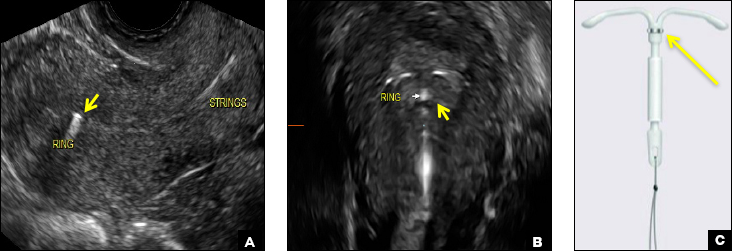

Paragard (Teva Women’s Health) is a nonhormonal IUD containing copper wire wrapped around its stem and solid copper bands on each crossbar. On ultrasonography, the stem is uniformly and markedly echogenic due to the copper wire.1,2,7

(A) Transvaginal ultrasound of the uterus demonstrates a uniformly and markedly echogenic stem seen in its entirety (short arrow). (B) 3D surface-rendered ultrasound of the uterus shows the solid copper bands on the crossbars (arrowhead). (C) Illustration of the Paragard IUD with the copper wire in the stem (long arrow) and solid copper bands on the crossbars (arrow heads).